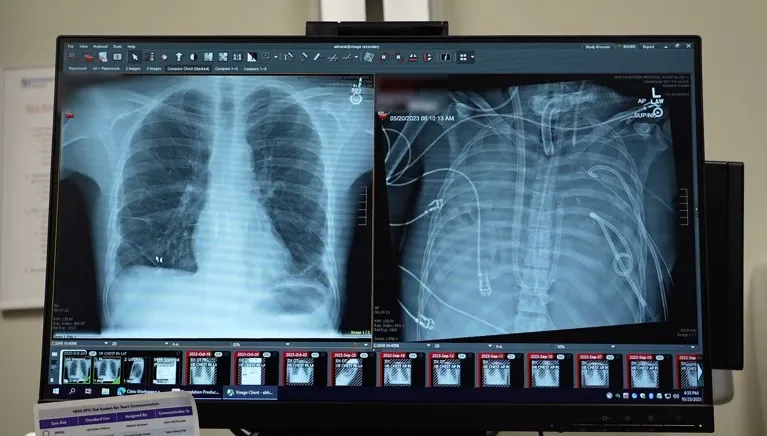

X-rays show a 33-year old patients’ new lungs (left) and old lungs (right) | Northwestern Medicine

The patient, a 33-year-old man, developed acute respiratory distress syndrome (ARDS) triggered by influenza B, complicated by a severe drug-resistant Pseudomonas infection. Conventional ventilators could not sustain his failing lungs, which were filled with pus, leading to sepsis, kidney failure, and cardiac arrest.

After 48 hours, a suitable donor became available, allowing for a successful double lung transplant. Two years later, the patient continues to enjoy normal lung function with no signs of organ rejection, showcasing the TAL system’s effectiveness and the surgical team's precision.